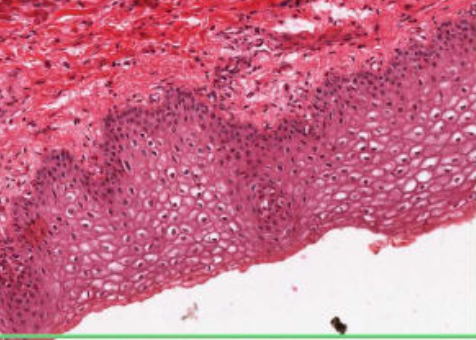

This is taken from the lip. What is the arrow pointing to?

The upper surface of the lip consists of hairy skin and the red arrow is pointing to a hair follicle

For the lips give

a) Mucosa

b) Fibers in connective tissue

c) Structures in the deep layers

a) Stratified squamous non-keratinising epithelium

b) sub-mucosa of collagen and elastin with small vessels to keep them moist

c) deep layers of skeletal muscle